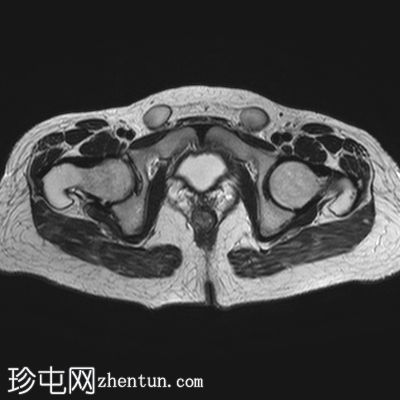

矢状位

T2加权像

子宫缺失

卵巢缺失

阴道下三分之一发育不全,上三分之二缺失

可见双侧腹股沟卵圆形结构,提示隐睾(右侧约2.4×2厘米,左侧约2.3×2厘米)

上述特征符合雄激素不敏感综合征(睾丸女性化综合征)的典型表现。

核型分析显示46XY染色体。